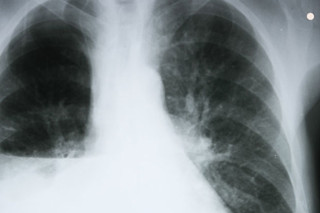

At first the clusters of rogue cells were so small that Martensen had no idea they existed. Nor was anyone looking for them inside the lean, ruddy-faced physician, who exercised most days and was an energetic presence as the chief historian at the National Institutes of Health. Then came a day in February 2011 when Martensen noticed a telltale node in his neck while taking a shower. “I felt no pain,” he recalls, “but I knew what it was. I told myself in the shower that this was cancer—and that from that moment on, my life would be different.”

Martensen initially thought it was lymphoma, cancer of the lymph glands, which has a higher survival rate than many other cancers. But after a biopsy, he was stunned to discover he had late-stage lung cancer, a disease that kills 85 percent of patients within a year. Most survive just a few months.

Once the diagnosis was made, two questions consumed the oncologists fighting to save Martensen’s life: What was the mechanism causing the mayhem in his cells? And how could they switch that mechanism off to stop the tumor growing inside him?